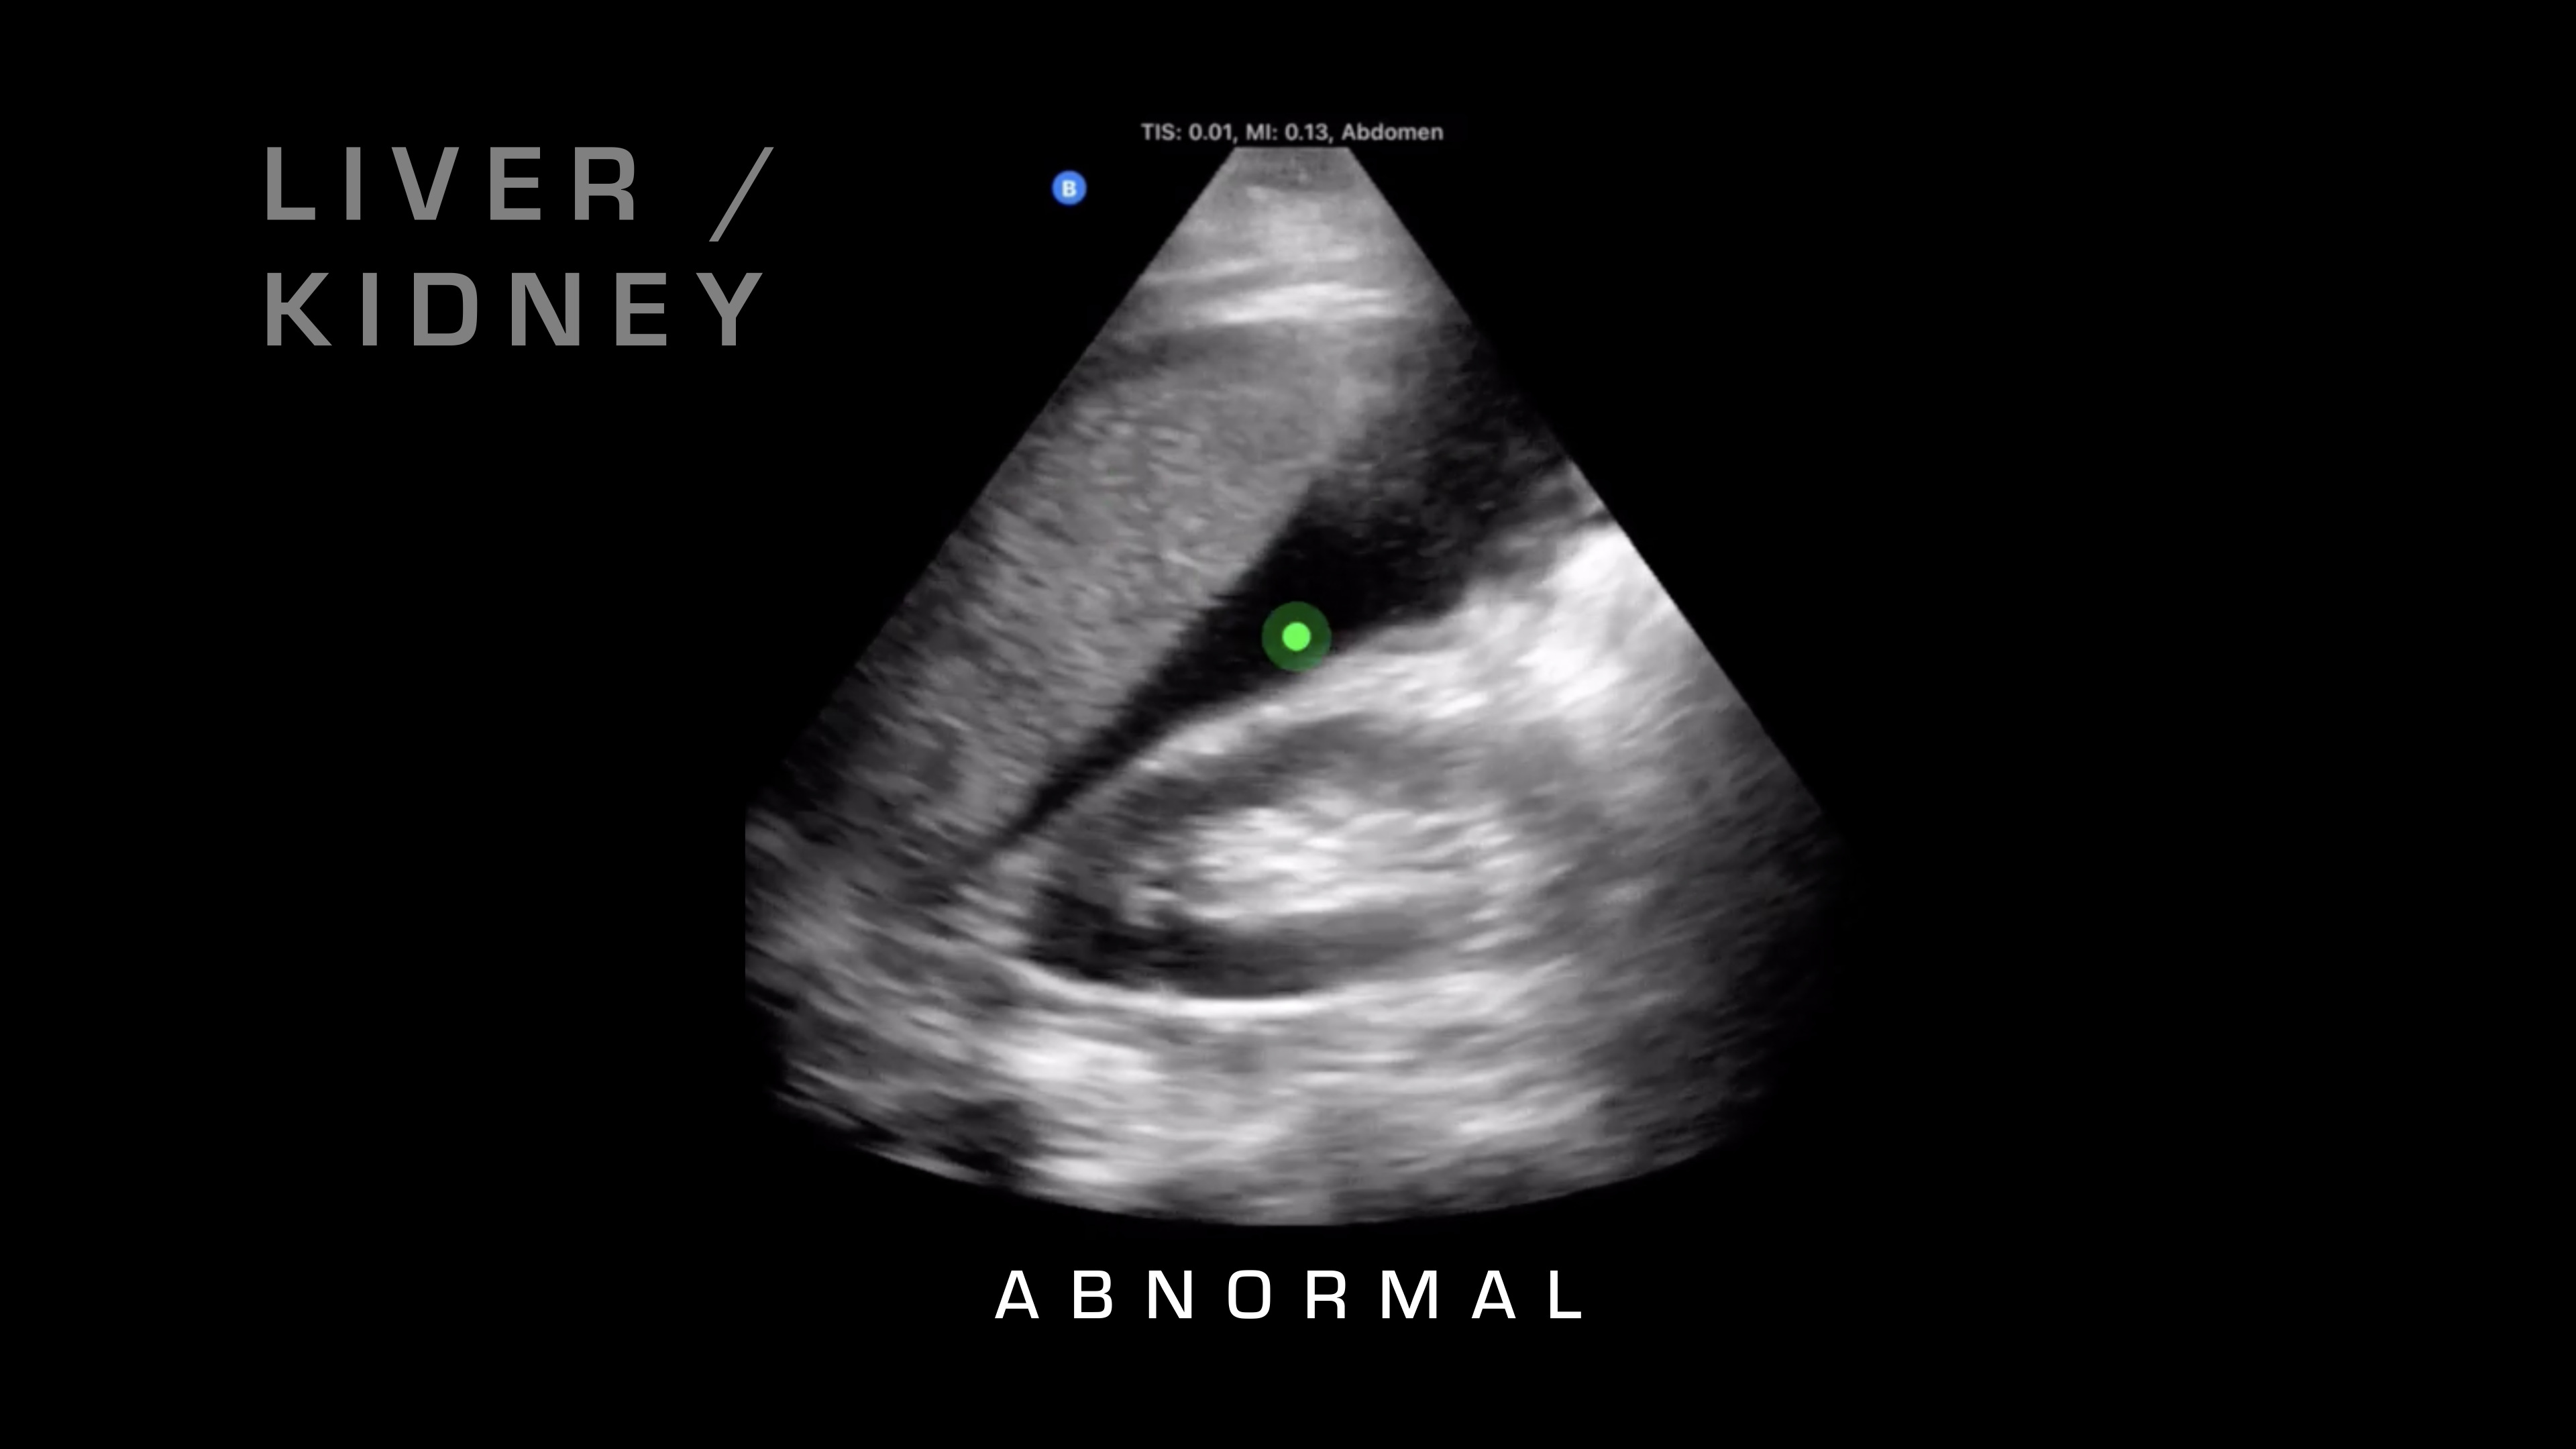

Liver & Kidney

If I want to go superficial, I'll swipe it down. If I want to go deeper, I'm going to swipe up and take a look. Next up, I'm going to go over on the right side of the patient, and what I'm going to be looking for is the liver and where that interfaces with the kidney. So there's a potential space there that shouldn't have any fluid between it, and if you see fluid between it, as you can see on this video here, then that's blood in the abdomen. So you know your patient is bleeding internally. That's obviously a risk for hemorrhagic shock, and that would warrant resuscitative care and rapid evacuation.